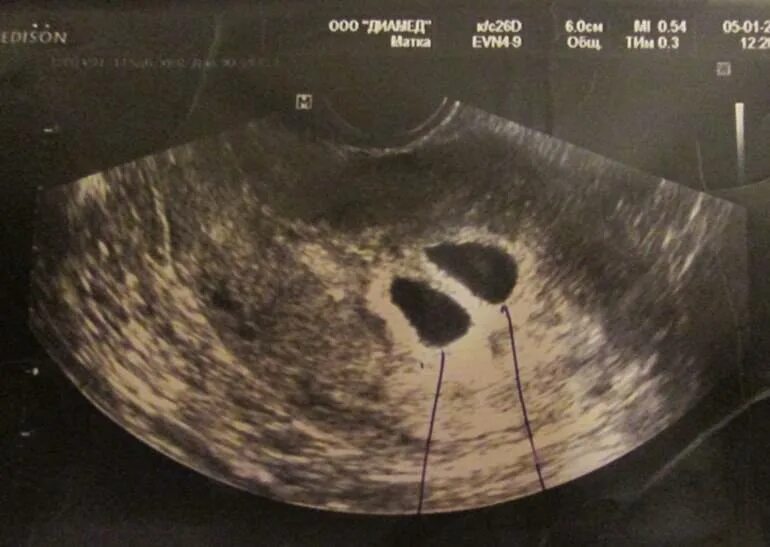

На каком сроке можно увидеть двойню